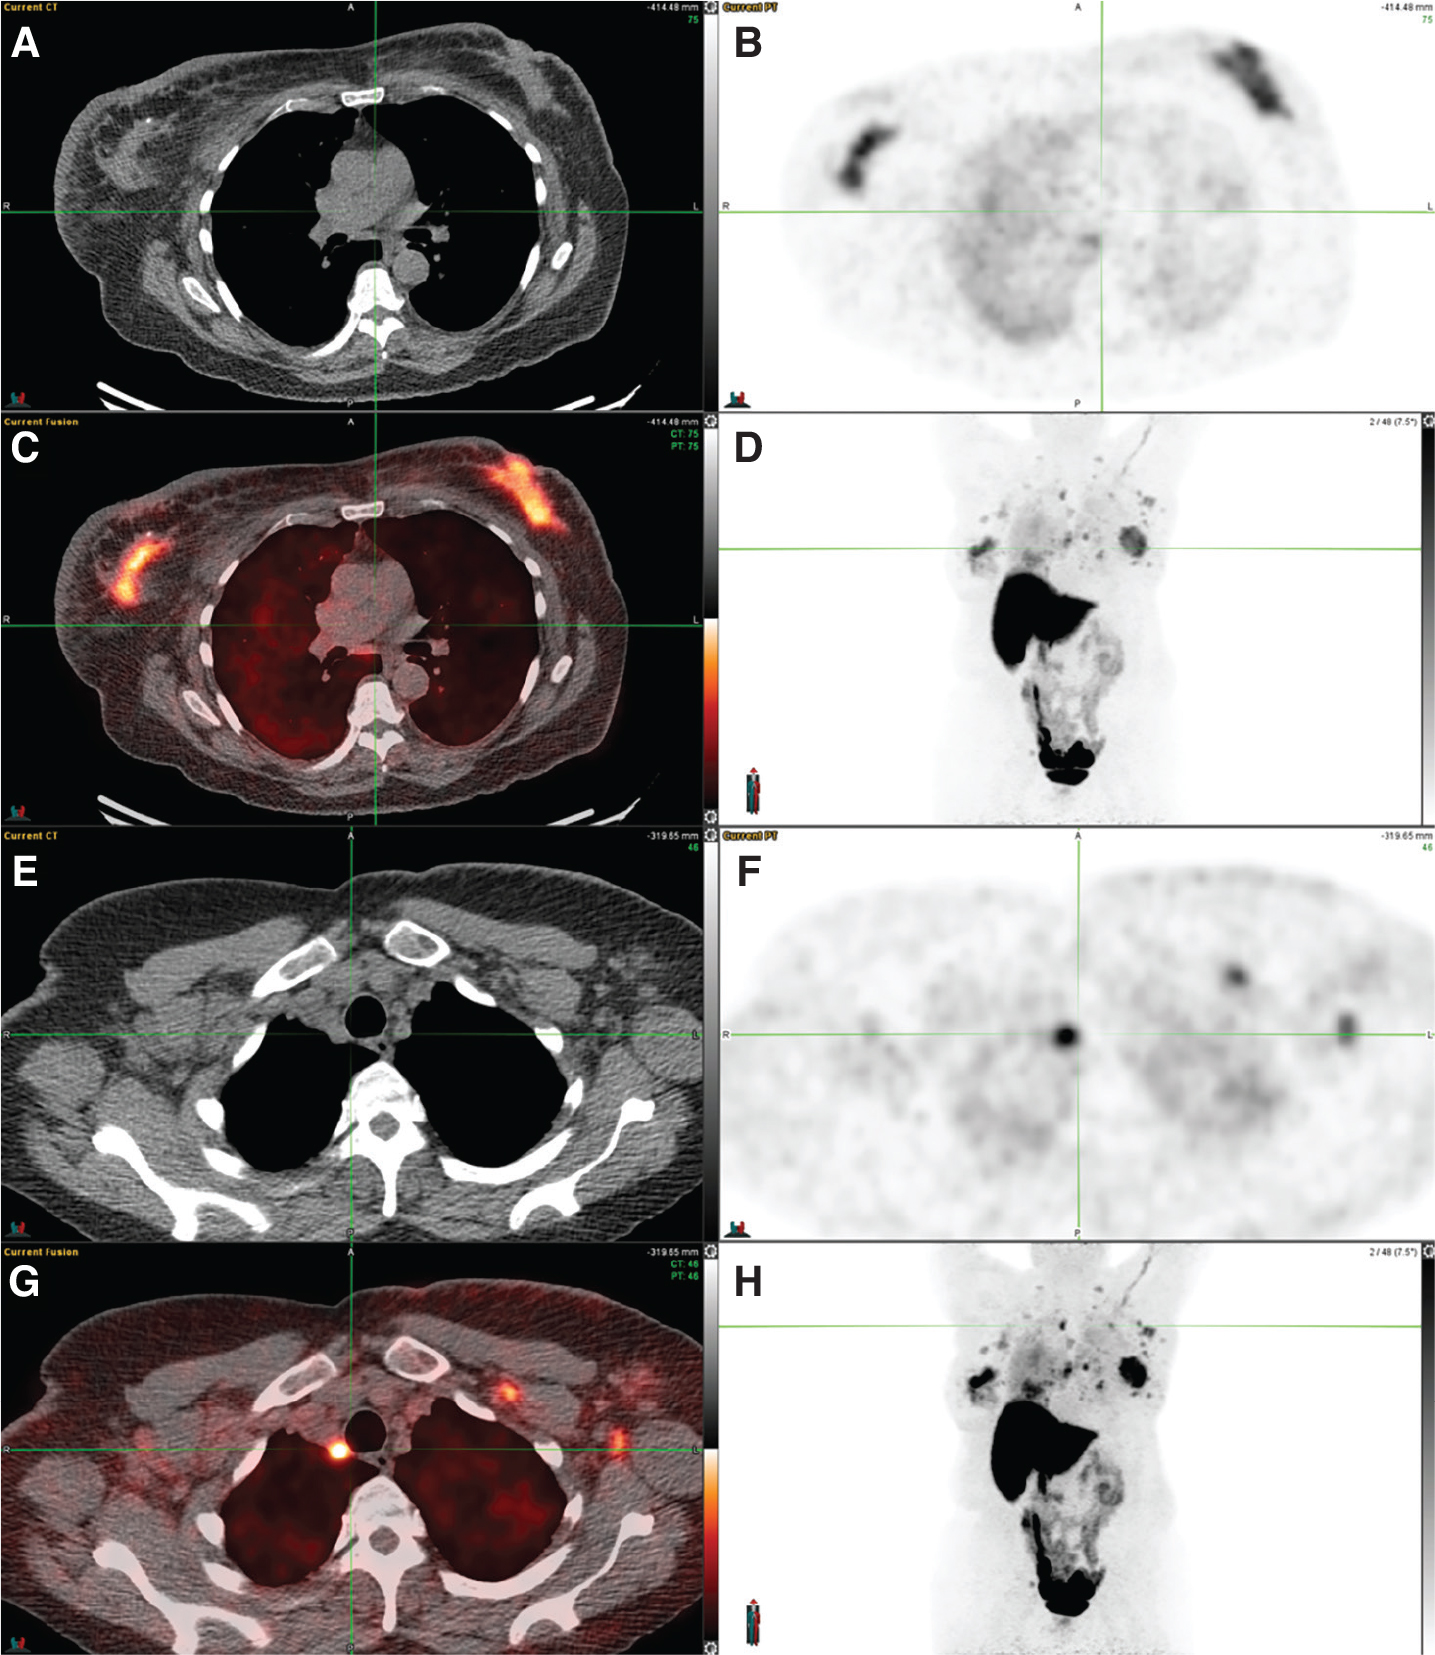

Fig 2

Figure 2. 18F-FES PET/CT in carcinoma breast. 18F-FES PET/CT in a patient with initially diagnosed left breast invasive ductal carcinoma (IDC), cT1cN0, ER+/PR+/HER-2 negative, Ki67 11%. Initially declined treatment and now with bilateral breast masses with Ki67 20%, bilateral lymphadenopathy, and pulmonary nodules. Images include: (A) axial CT, (B) axial FES PET, (C) fused axial PET/CT, (D) maximum intensity projection (MIP) image, (E) axial CT, (F) axial FES PET, (G) fused axial PET/CT, and (H) MIP image. 18F-FES PET/CT demonstrates increased FES uptake in the bilateral breast masses (images A-D), lymph nodes in the bilateral axillae, subpectoral regions, and mediastinum (images E-H), and bilateral pulmonary nodules (lung windows not included).